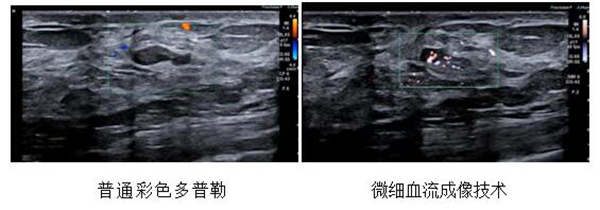

2、 微细血流成像技术

是目前世界上最新的血流成像技术,可捕捉超微细血流及超低速血流信号,能够应用于肝脏、肾脏、膀胱、甲状腺、乳腺等脏器良恶性肿瘤的鉴别,移植器官术前、术后的评估,浅表淋巴结血流分析、诊断及治疗有效性的评估,深静脉血栓、动脉粥样硬化斑块新生血管的检测等诸多方面。SMI具有无创、无辐射、无需注射造影剂等优点,具有很高的临床应用价值。